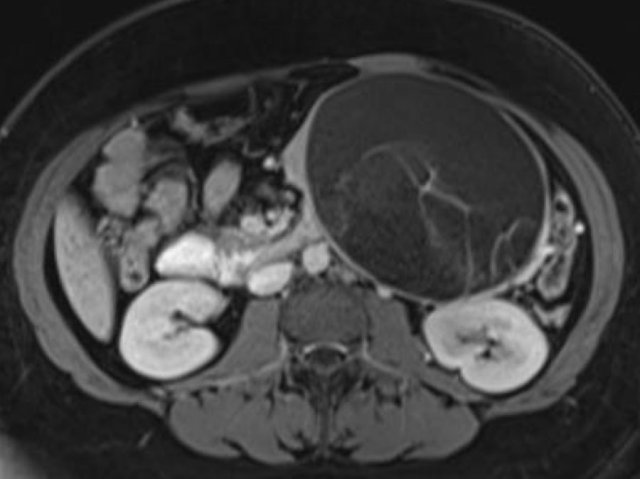

In a 73 year old male a hypoechoic lesion was found in the pancreatic body, that looked like a cystic lesion.

CT also identifies the lesion but isn't of much help.

Continue with the MRI.

The heavily T2WI nicely demonstrates the multicystic lesion with the connection to the pancreatic duct.

This was diagnosed as a branch-duct IPMN.